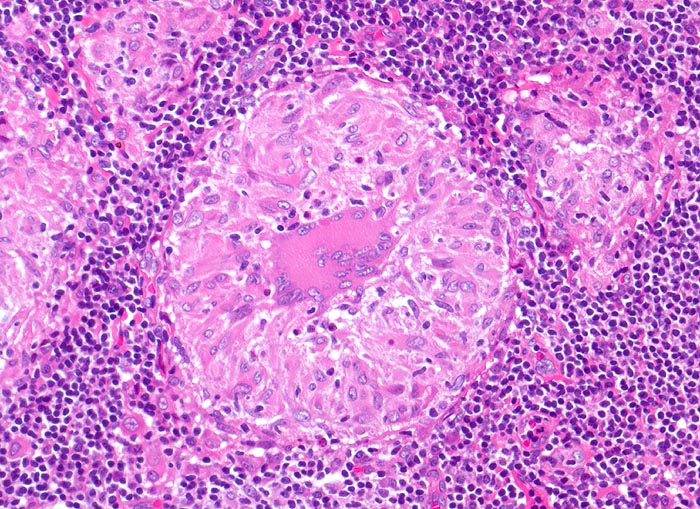

Lymphknotensarkoidose (Morbus Boeck)

In der Bildmitte ein rein produktives Granulom mit zentral gelegener Riesenzelle vom Langhanstyp und Epitheloidzellen (längsovale, schuhsohlenartige Kerne und reichlich Zytoplasma).

Vergrösserte inguinale Lymphknoten bei bekannter Sarkoidose mit Befall der Lungen.

Epitheloidzellige Granulome sind nicht spezifisch für Sarkoidose. Sie können beispielsweise bei guter Abwehrlage auch bei einer Tuberkulose auftreten. Seltenerweise kann man auch bei einer Sarkoidose verkäsende Granulome nachweisen. Die Diagnose einer Sarkoidose sollte erst nach Ausschluss anderer granulomatöser Entzündungen gestellt werden. Zum histologischen Ausschluss einer rein produktiven Tuberkulose wäre es notwendig, eine Ziehl-Neelsen-Färbung durchzuführen, um die säurefesten stäbchenförmigen Tuberkelbakterien nachzuweisen. Diese Bakterien wären in den Epitheloidzellen und vor allem auch in den Riesenzellen zu finden. Bei relativ guter Abwehrlage können die säurefesten Stäbchen aber auch bei der Tuberkulose fehlen.